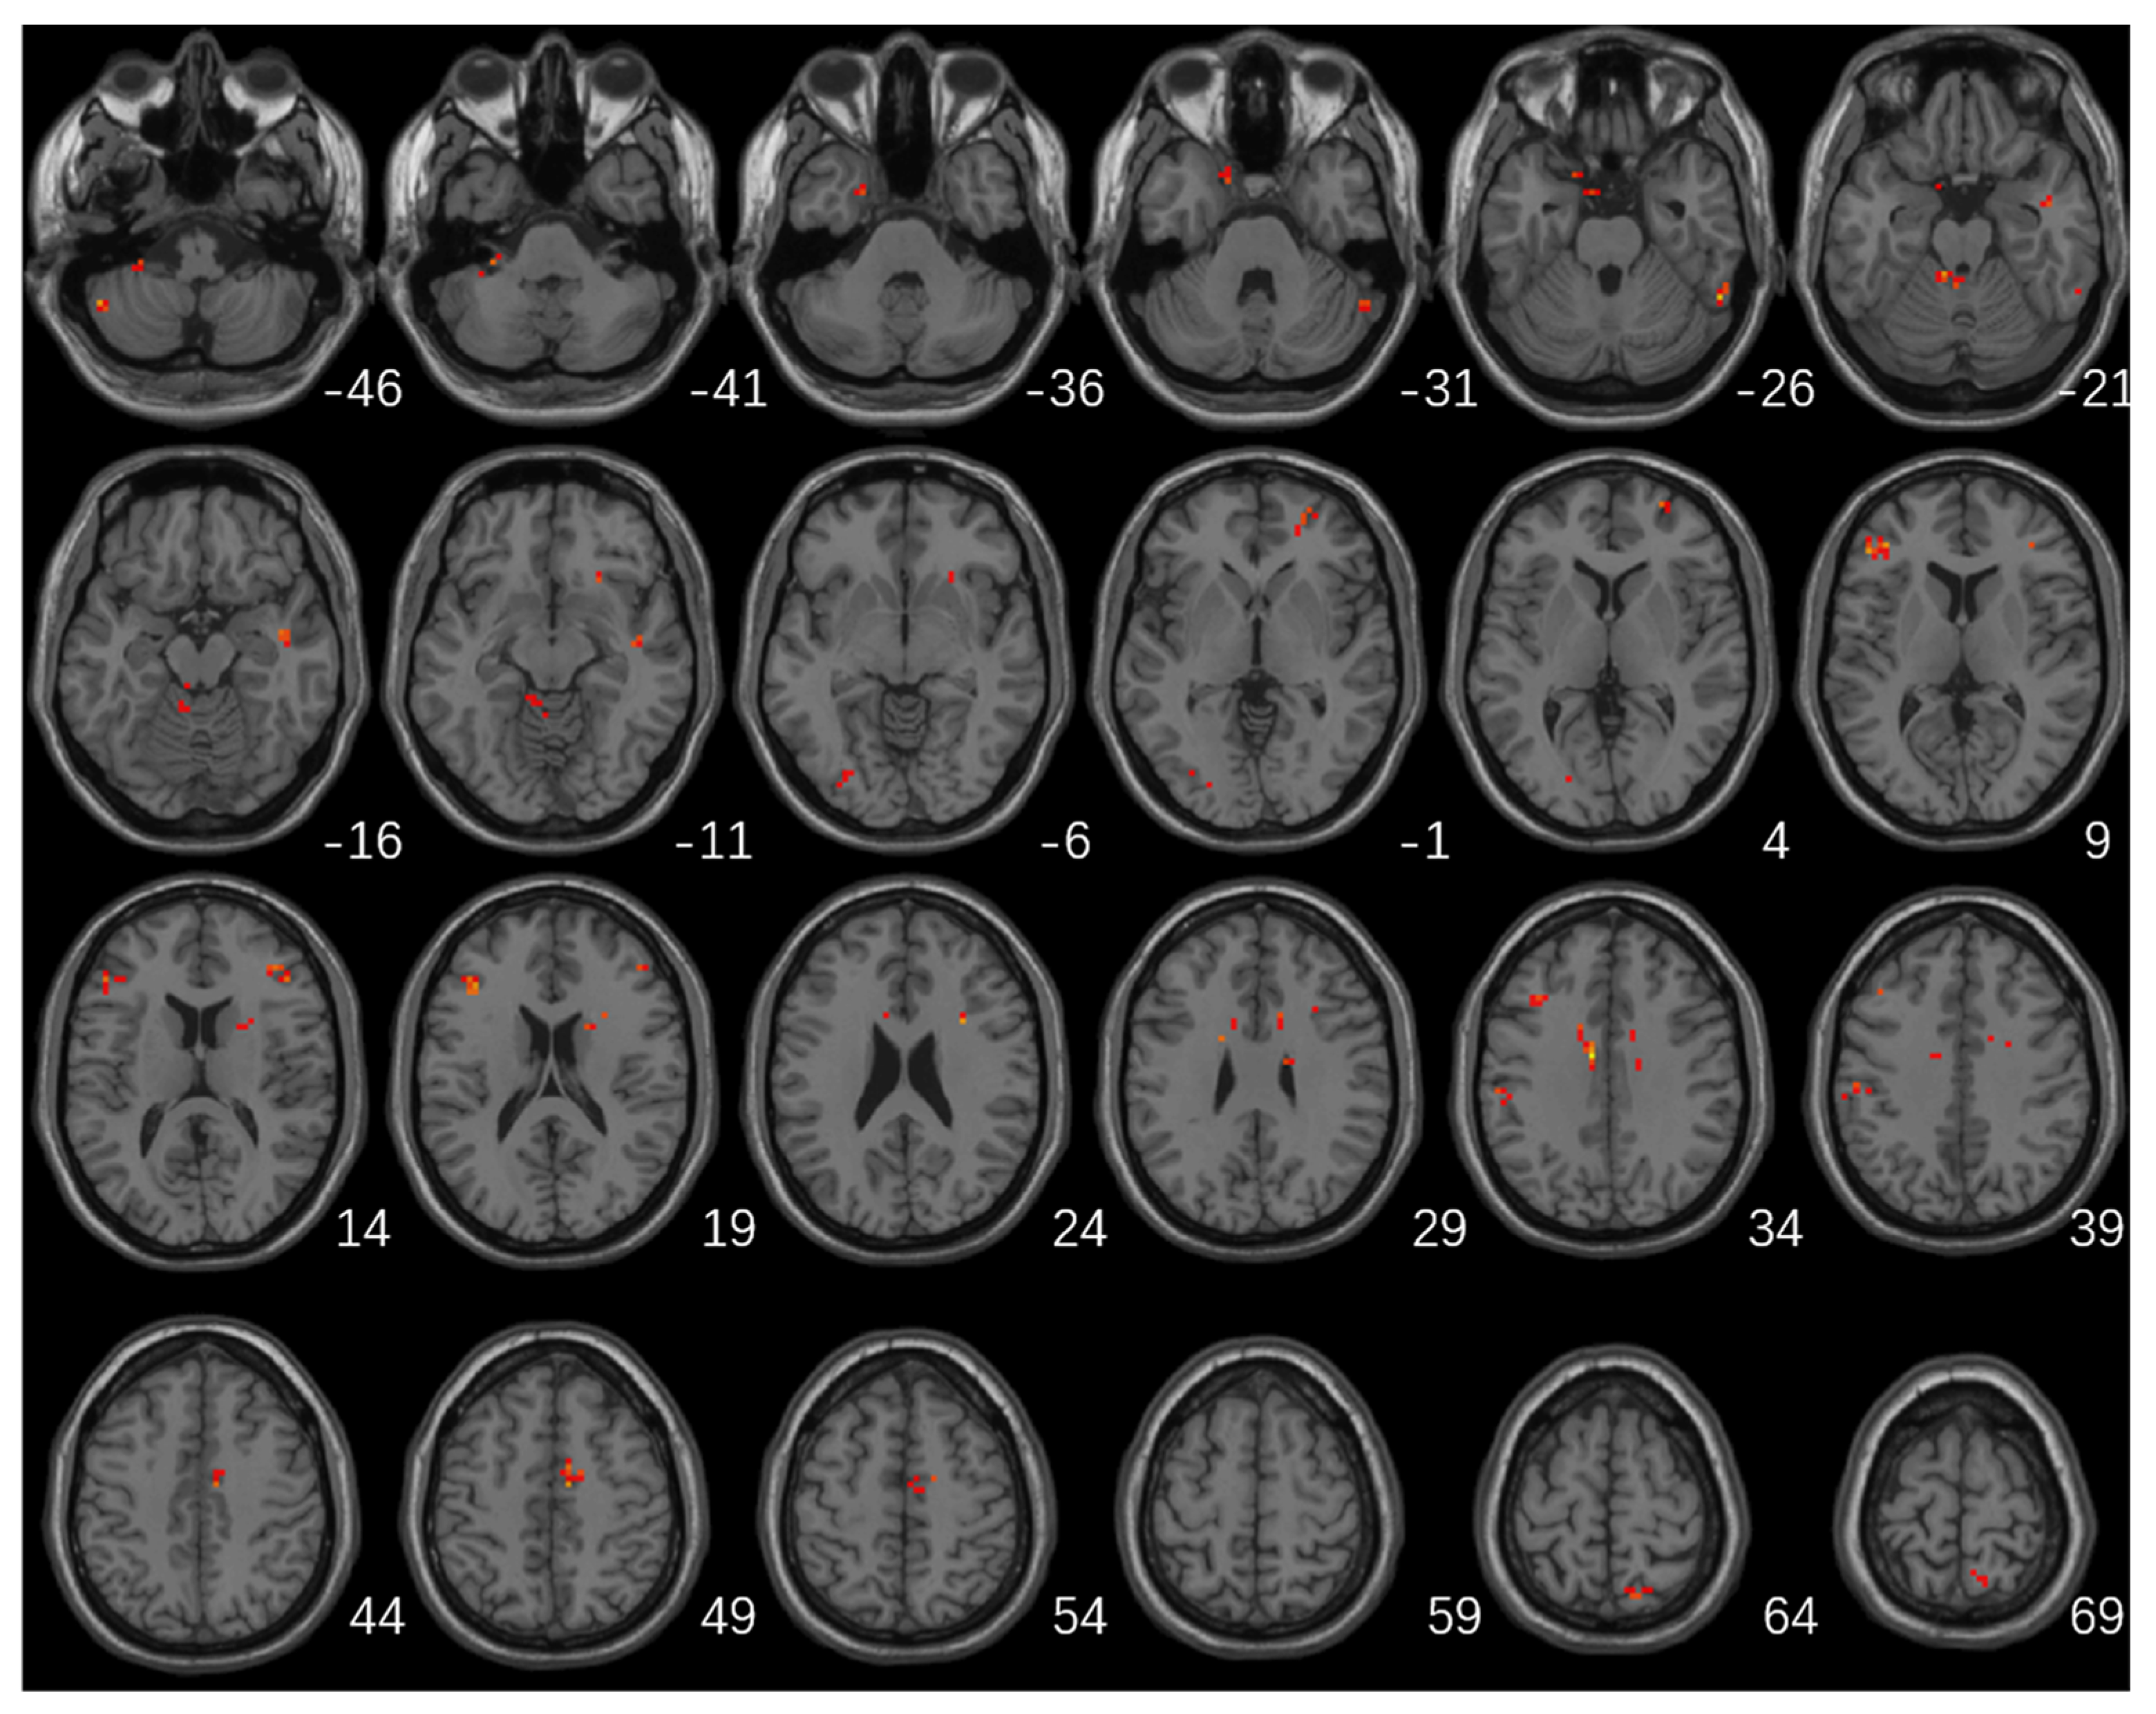

Significant differences in fALFF values among the three groups were mainly located in the left cerebellum, cerebellum posterior lobe, bilateral frontal lobes, bilateral temporal lobes, left occipital lobe, left inferior parietal lobule, right caudate, and right precuneus (Table 2; Figure 1).

Figure 1.

Brain regions with significant differences in fALFF among the three groups (GRF multiple comparison correction, p < 0.01 at the voxel level and p < 0.05 at the cluster level).

The higher fALFF values within the left cerebellum, posterior cerebellum lobe, bilateral temporal lobes, and brainstem, and the lower fALFF values within the bilateral frontal lobes, right basal ganglia areas, and left inferior parietal lobule were identified in PD-A patients compared with HCs (Table 3, Figure 2). Compared with HCs, PD-NA patients showed increased fALFF values in the left cerebellum and cerebellum posterior lobe. In contrast, decreased fALFF values were noted in the right cuneus and left superior parietal lobe (Table 3, Figure 2). When comparing the two PD groups, increased fALFF values of the right precuneus were found in PD-A patients. In contrast, decreased fALFF values were demonstrated in the bilateral frontal lobes, bilateral basal ganglia areas, left inferior parietal lobule, and left occipital lobe (Table 3, Figure 2). The fALFF values in the right precuneus (r = 0.54, p < 0.001) were positively correlated with HAMA scores of PD-A patients (Figure 3). Furthermore, the fALFF values in the left caudate were negatively correlated with HAMA scores of PD-A patients (r = −0.60, p < 0.001) according to Pearson’s correlation analysis (Figure 4).